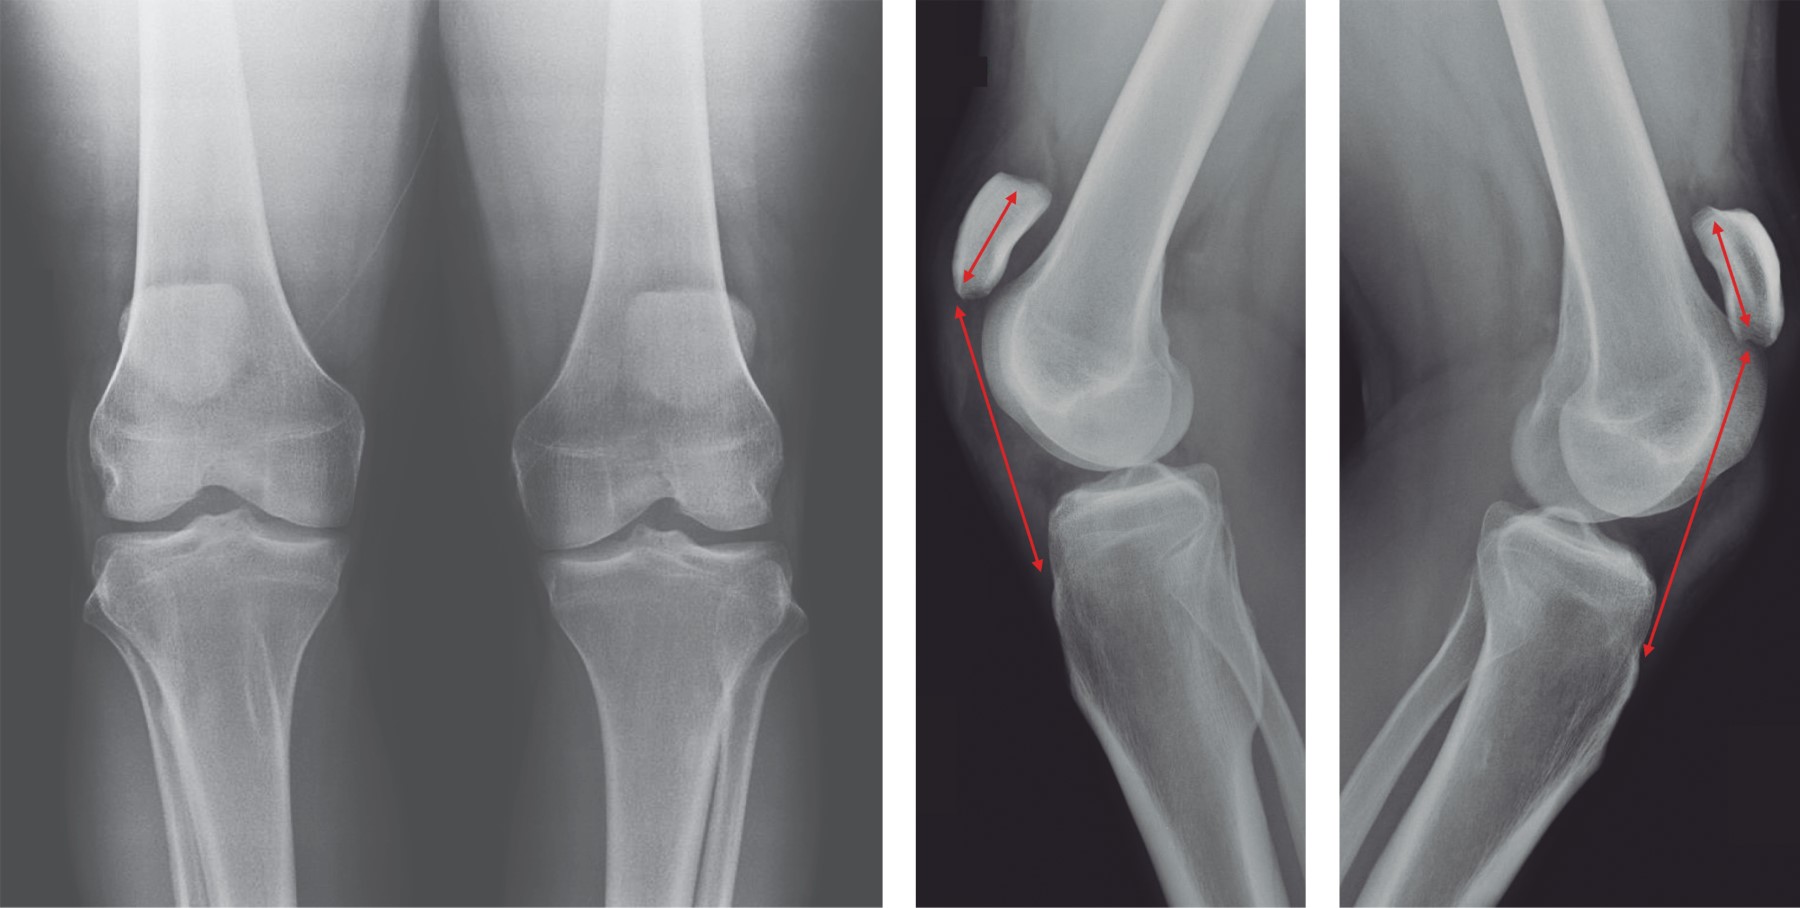

En las radiografías anteroposterior y lateral de rodillas se utilizó el índice de Insall-Salvati y se descartaron lesiones óseas (Figura 2). En el ultrasonido se encontró rotura bilateral completa de tendones patelares. Los laboratorios de rutina se mostraron dentro de la normalidad.

Todos los casos reportaron síntomas similares (dolor, inflamación, incapacidad para levantar activamente la pierna) que resultan muy generales y requieren alto nivel de sospecha para evitar un diagnóstico erróneo. En este caso, la valoración clínica inmediata acompañada de radiografías simples y ultrasonido (por su inmediata disponibilidad) ayudaron a confirmaron el diagnóstico. En las radiografías laterales un índice de Insall-Salvati > 1.2 (patela alta) sugirió rotura completa del tendón patelar;35 en el ultrasonido se estimó una tasa de falsos positivos hasta en un tercio de los casos, en particular en pacientes obesos, por lo que la resonancia magnética se mantiene como el estándar de oro.36,37 Se estima que un tercio de las roturas aisladas son subdiagnosticadas en la consulta inicial, lo que lleva a un tratamiento tardío y una posible disminución de la función.25

Figura 2